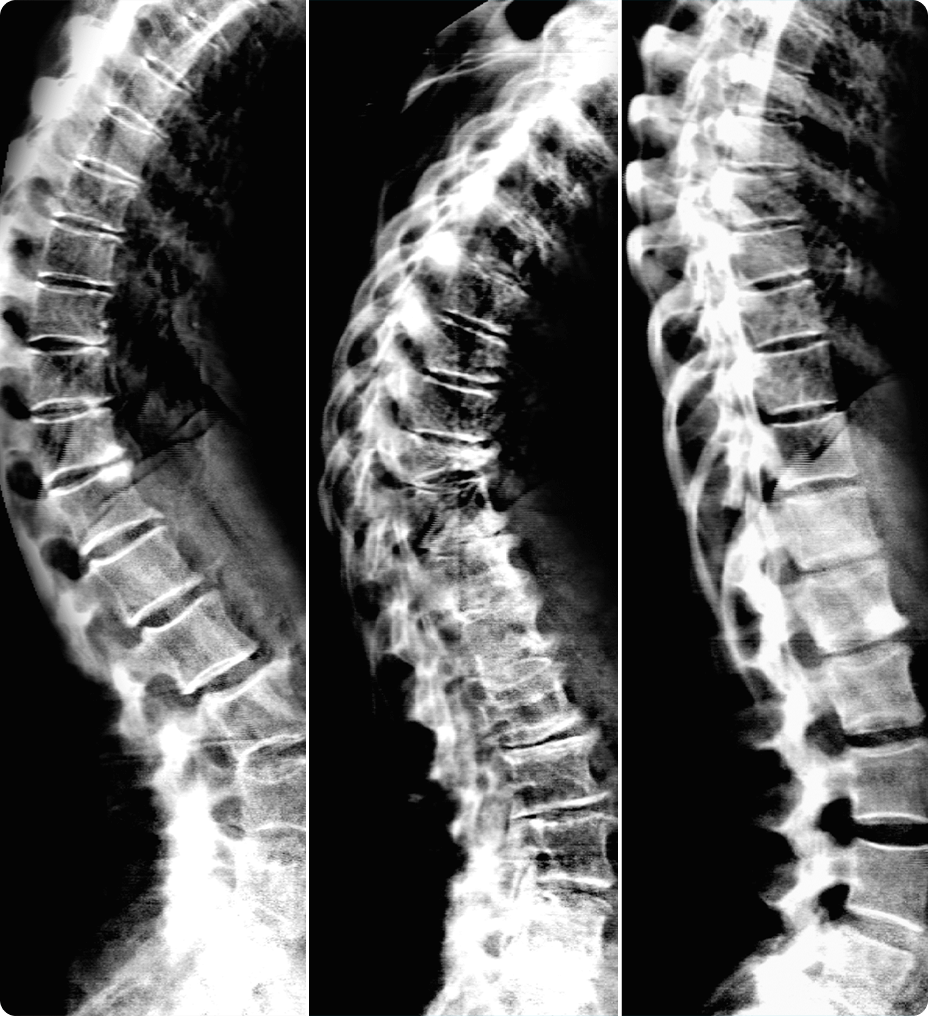

• Zero-click bone segmentation for head, neck, and other

anatomy.

• Automated real-time fast tracking for all vasculature.